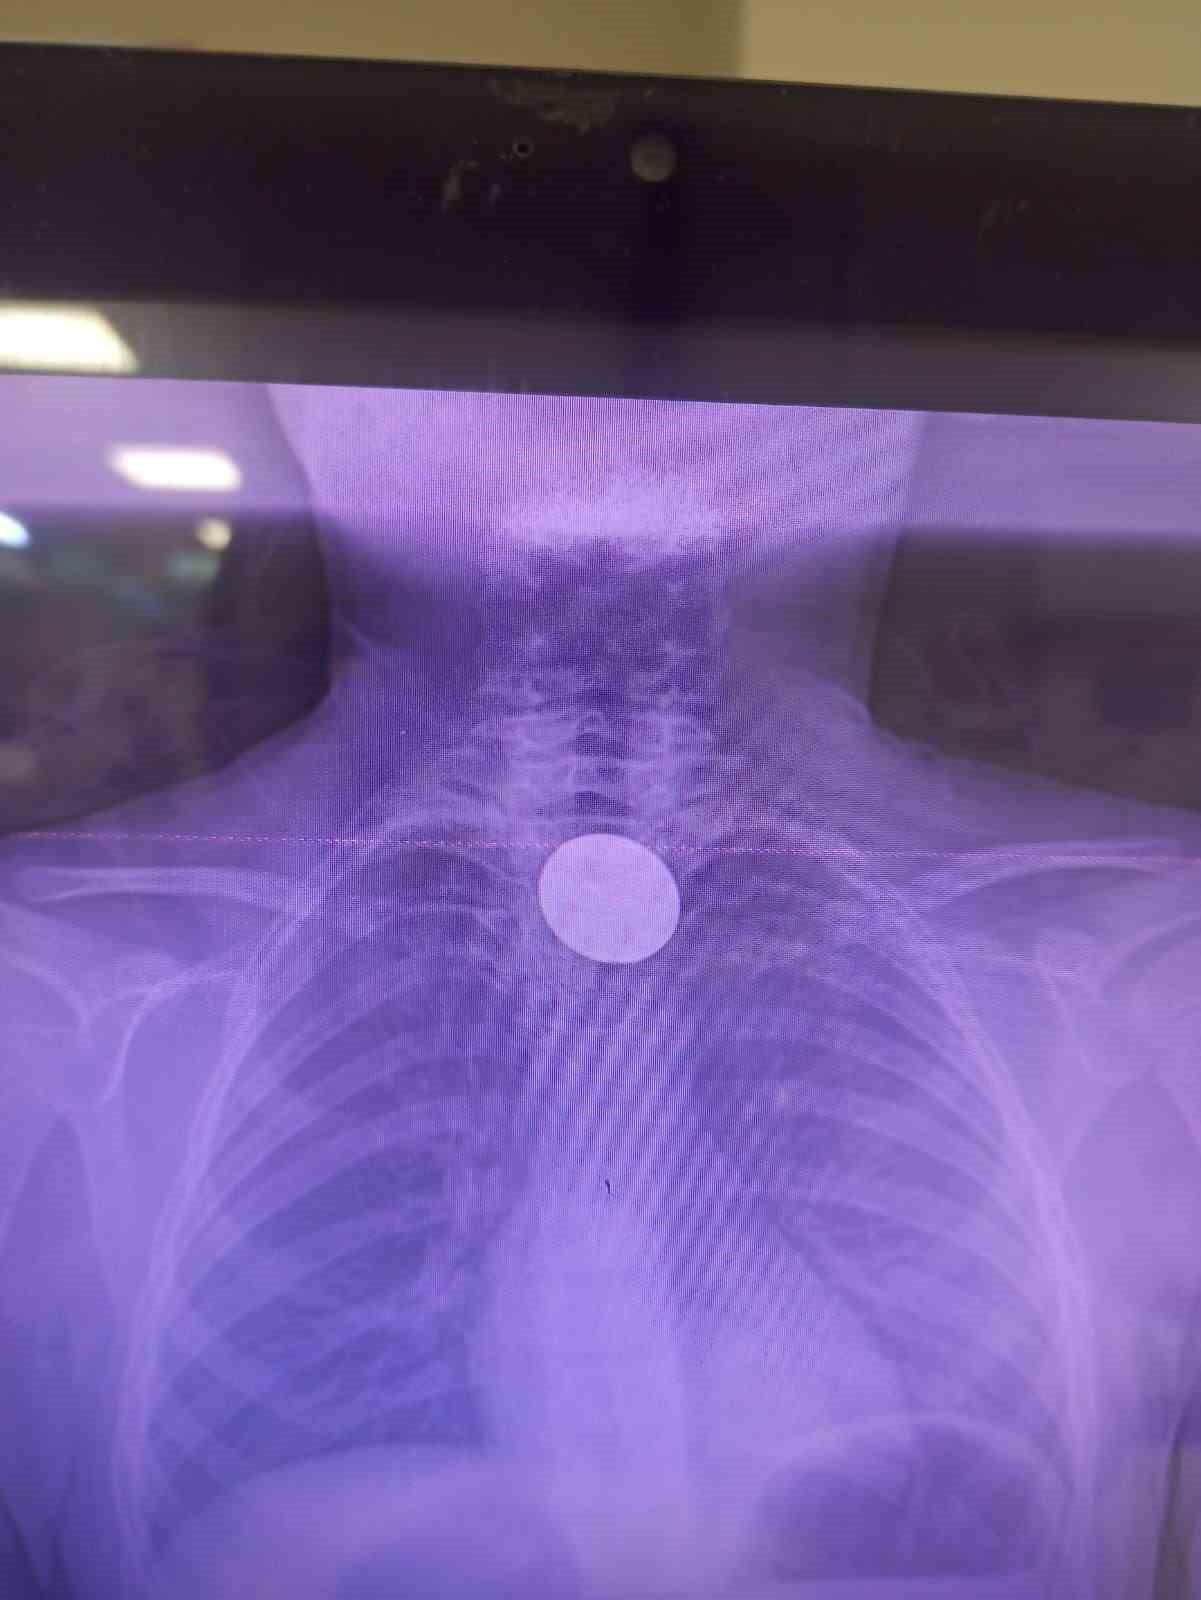

Yabancı cisim yutma şikayetiyle ailesi tarafından Siirt Eğitim ve Araştırma Hastanesine getirilen 8 yaşındaki Y.K., yapılan ilk değerlendirme ve görüntüleme tetkiklerinin ardından ilgili branşlarca operasyona alındı. Y.K.’nın yemek borusuna kadar ilerlediği tespit edilen madeni para, gastroenteroloji uzmanı Dr. Yaren Dirik ve kulak burun boğaz hekimi Yasin Gökçınar tarafından müdahale edilerek çıkartıldı. Operasyonun ardından bir süre gözlem altında tutulan Y.K., tedavisinin tamamlanmasıyla taburcu edildi.

Siirt Eğitim ve Araştırma Hastanesi Başhekim Yardımcısı Uzman Dr. Burak Özkan, çocuk hastalarda yabancı cisim yutma vakalarının ciddi riskler oluşturabileceğini söyledi. Uzm. Dr. Özkan, “Hastanemize başvuran 8 yaşındaki hastamızın yemek borusuna kaçan madeni para, gastroenteroloji ve KBB ekiplerimizin koordineli ve titiz çalışmasıyla herhangi bir komplikasyona yol açmadan başarılı bir şekilde çıkarılmıştır. Operasyon süreci sorunsuz geçmiş olup hastamızın genel durumu iyidir” dedi.